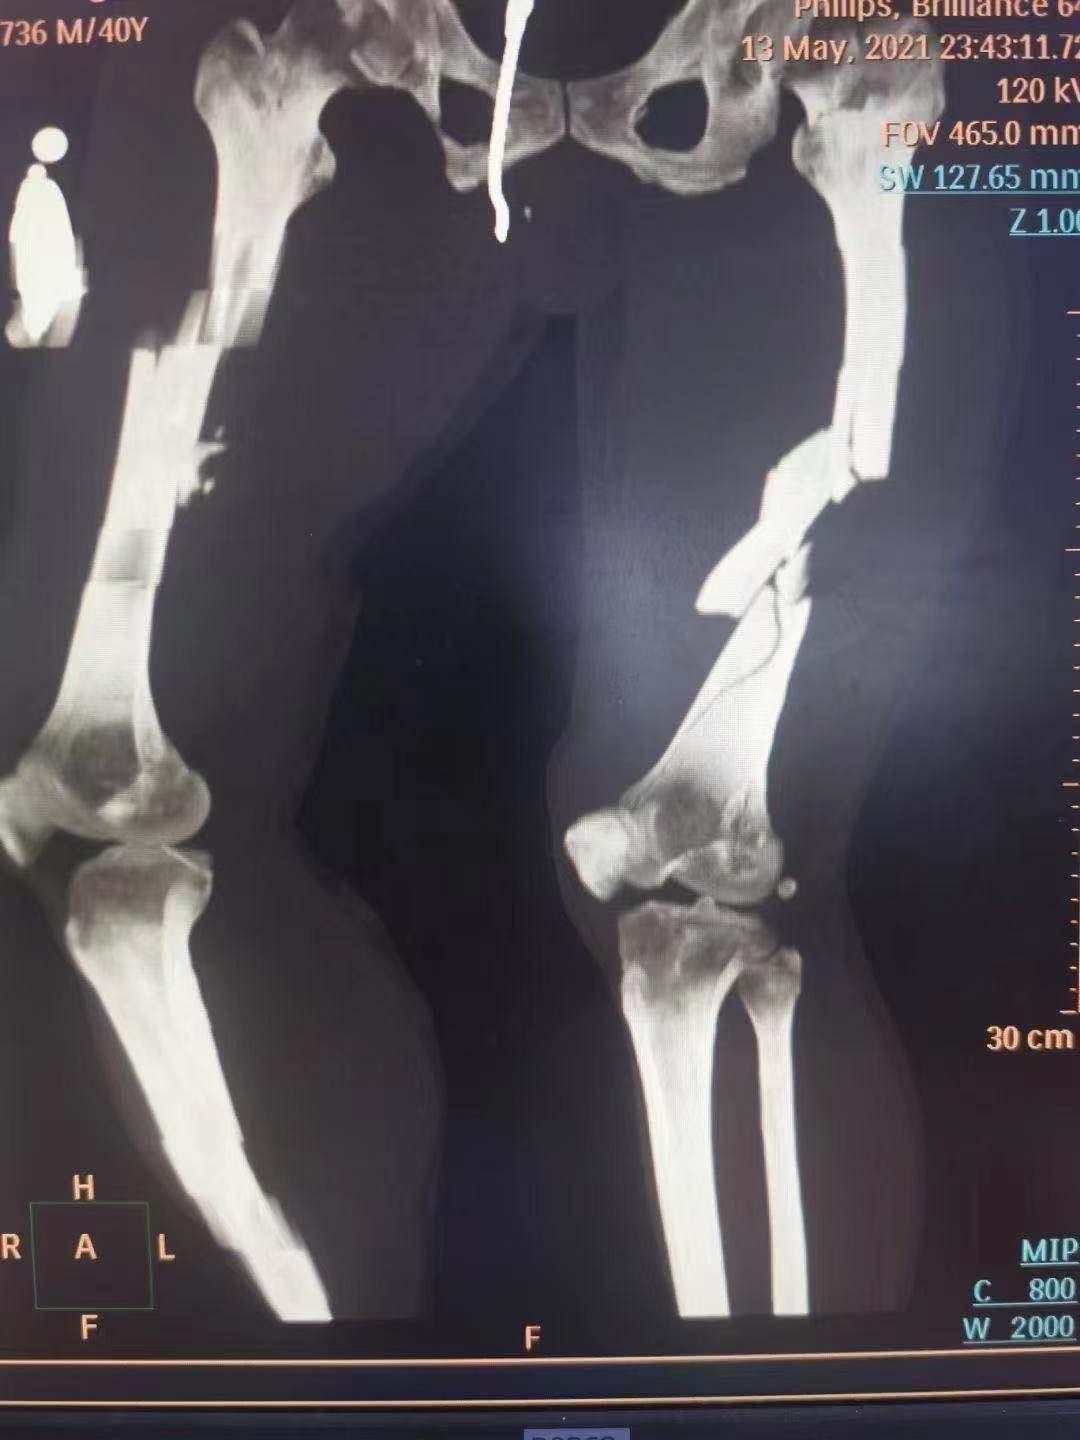

患者休克、头面部严重撕脱伤、双下肢多处粉碎性骨折、颈椎第1、4、7椎体骨折等严重多发伤。急诊科立即启动急救绿色通道,经骨科、普外、神经外科多学科急会诊,确认患者无脑部及内脏损伤后,由骨科紧急实施手术,无影灯下上演“生死时速”……

凌晨的手术室内灯火通明。在麻醉科的配合下,主刀医生首先为男性患者行头皮撕脱伤清创缝合术,左、右侧股骨干骨折切开复位内固定术,左内踝关节骨折切开复位内固定术。紧接着,医生们未有片刻休息,又继续为女性患者实行左股骨干骨折切开复位内固定术。